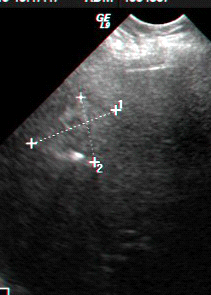

- באולטרה-סאונד אפשר להדגים גוש כיסתי. האולטרה-סאונד הפך לאמצעי האבחנתי החשוב בכיסיות של הכבד (תצלום 24.10).

בבדיקות מעבדה: תפקודי הכבד לרוב תקינים, אך תיתכן עליה קלה ברמת האנזימים. האבחנה מתבצעת על ידי טומוגרפיה ממוחשבת (תמונה 26.10 ) או תהודה מגנטית (תמונה 27.10) כך שבדרך כלל אין צורך לקחת ביופסיה. באולטרה-סאונד ניתן להדגים גוש בכבד (תמונה 28.10).

| תמונה 28.10 : הדגמה של FNH באולטרה-סאונד כבד. השנתות מצביעות על גודל השאת. |